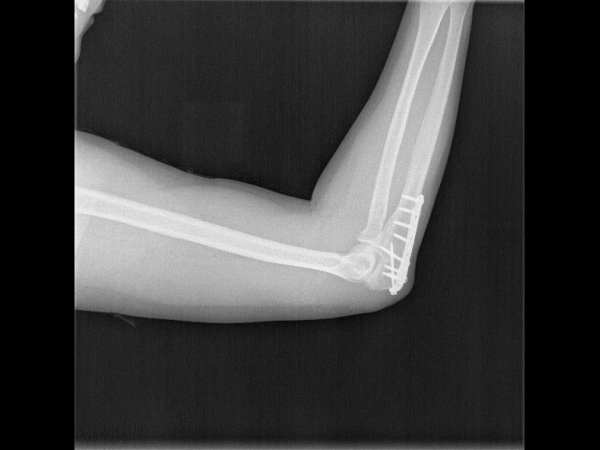

Elongated Combi hole in the neck and shaft facilitate plate adjustment and allow locking or compression options.

The combi-hole pro- vides flexibility of axial compression and locking capability throughout the length of the plate shaft.

Various screws target to help stabilize the coronoid, thereby helping to restore bony and ligamentous struc- tures, which are important for elbow-joint stability.

Kirschner wire holes accept Kirschner wires (up to 1.5 mm) to temporarily fix the plate to the bone, to temporarily reduce articular fragments, and to confirm the location of the plate, relative to the bone.